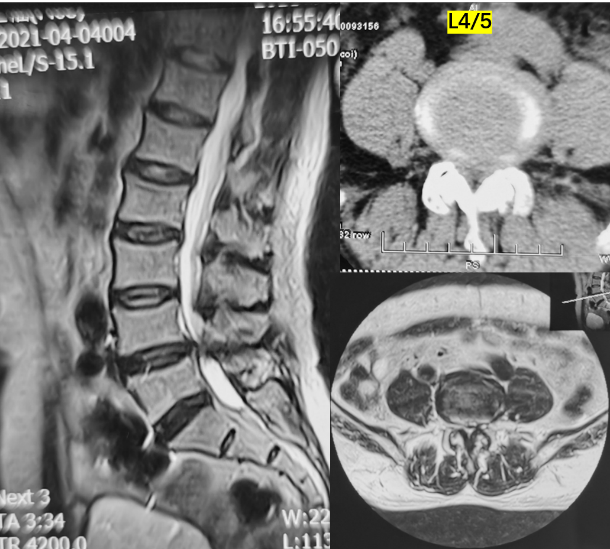

术前影像

第三例51岁女性患者,因“右下肢放射性疼痛、麻木1年,加重1月余”入院,发病以来反复多次保守治疗无效。入院后经术前讨论、评估,制定治疗方案,行OLIF手术,该病例采用后路经皮椎弓根螺钉内固定。次日患者下地活动,下肢症状消失,疗效满意。